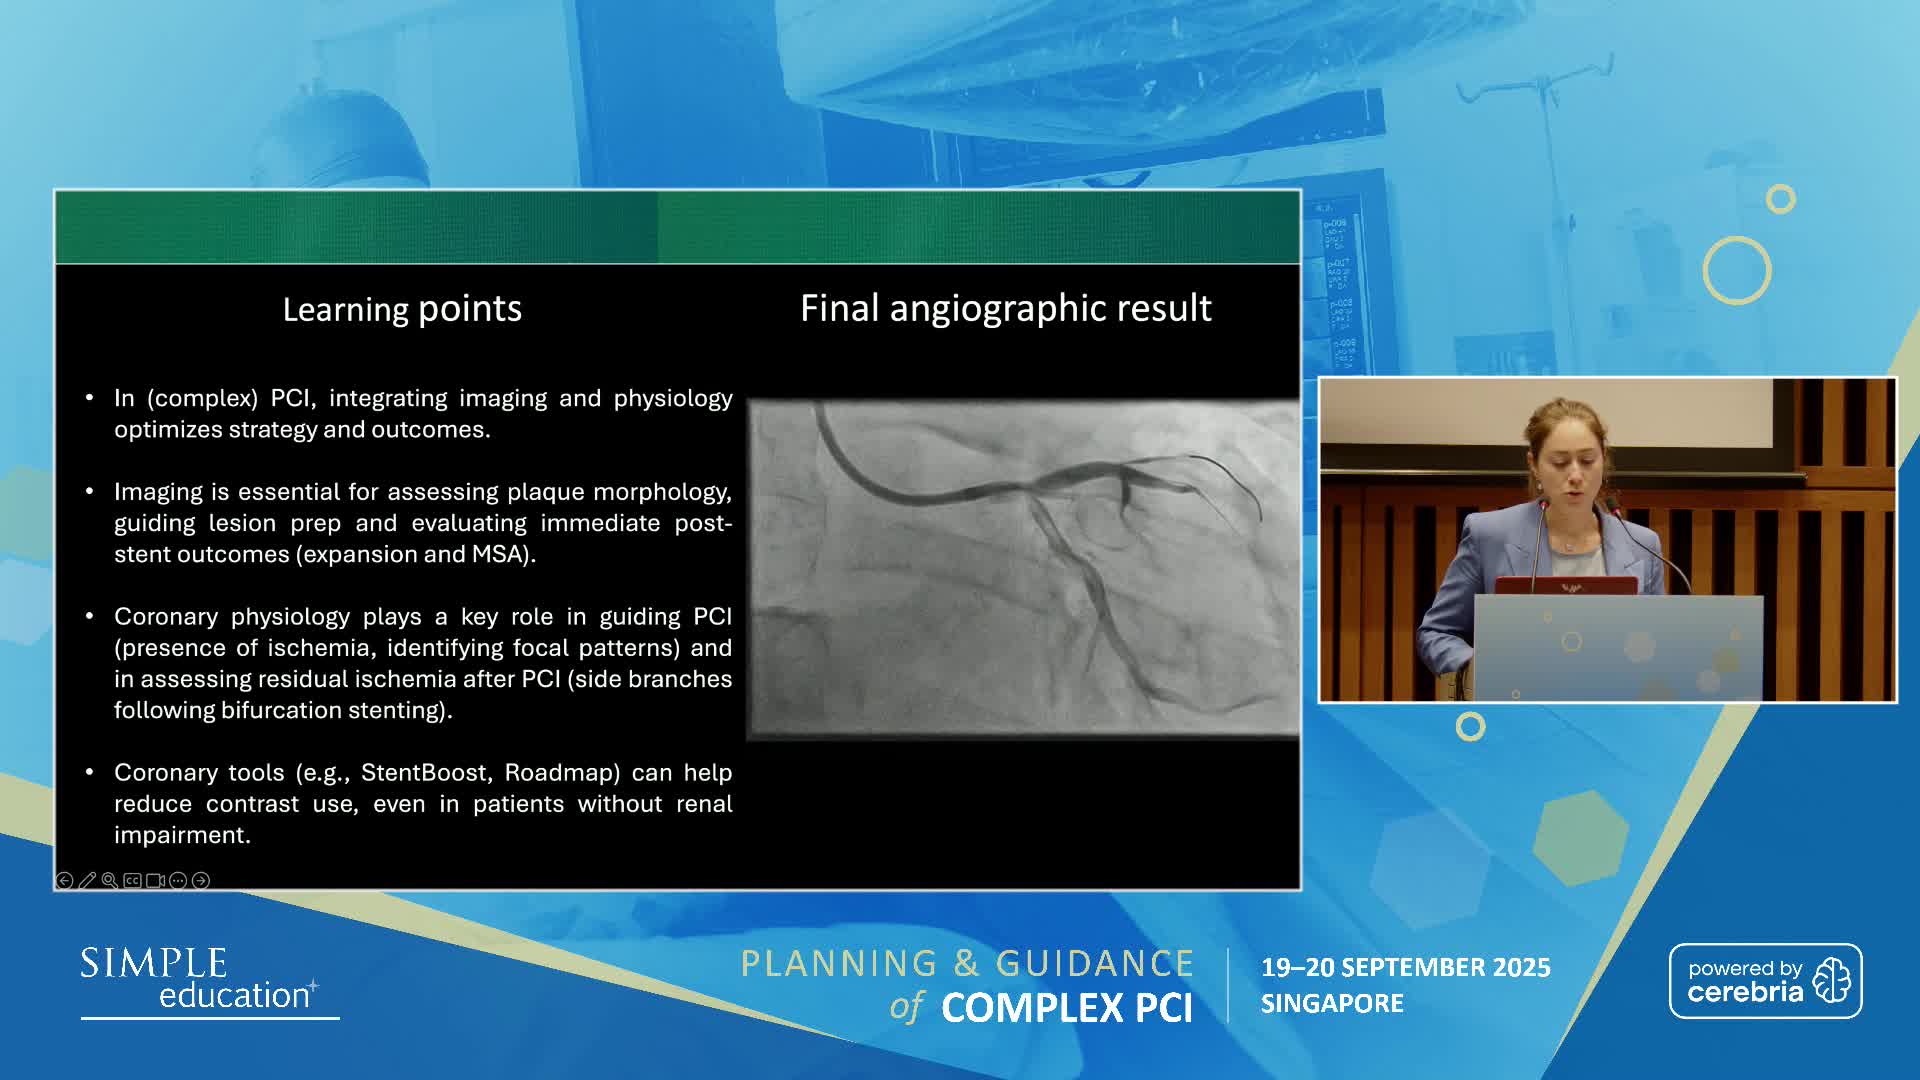

Planning and guidance of complex percutaneous coronary interventions - June 2023 Day One

Planning and guidance of complex percutaneous coronary interventions - June 2023 Day Two